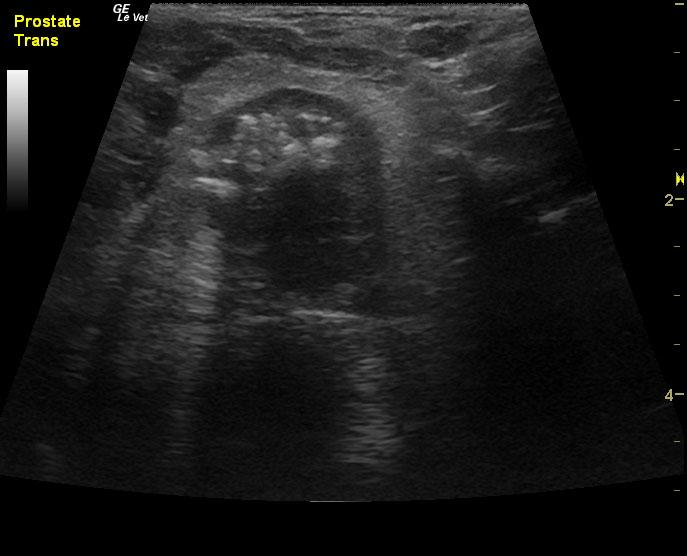

A 14-year-old neutered male Pomeranian dog was presented for evaluation of pollakiuria, diarrhea, inappetence, and lethargy. Abnormalities on physical examination included a painful, enlarged and symmetrical prostate, a very large and firm urinary bladder that could be expressed, and a grade III/VI heart murmur. On survey thoracic radiographs, calcification of the prostate gland was evident.

A 14-year-old neutered male Pomeranian dog was presented for evaluation of pollakiuria, diarrhea, inappetence, and lethargy. Abnormalities on physical examination included a painful, enlarged and symmetrical prostate, a very large and firm urinary bladder that could be expressed, and a grade III/VI heart murmur. On survey thoracic radiographs, calcification of the prostate gland was evident.